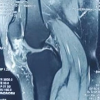

The iliac crest physis is unfused (Risser stage 3). MRI was performed to confirm the continuity of the cortex/medulla with adjacent bone, the size of the stem, and surrounding soft tissue (Fig. 2).

Furthermore, we have also observed that the stem connecting the tumor to the ilium with no evidence of bone destruction and invasion of the surrounding tissue. According to these imaging findings, the patient was diagnosed with osteochondroma. We did not perform a CT scan or 3D model printing as it was not required for surgical planning due to the relatively safe location of the tumor.